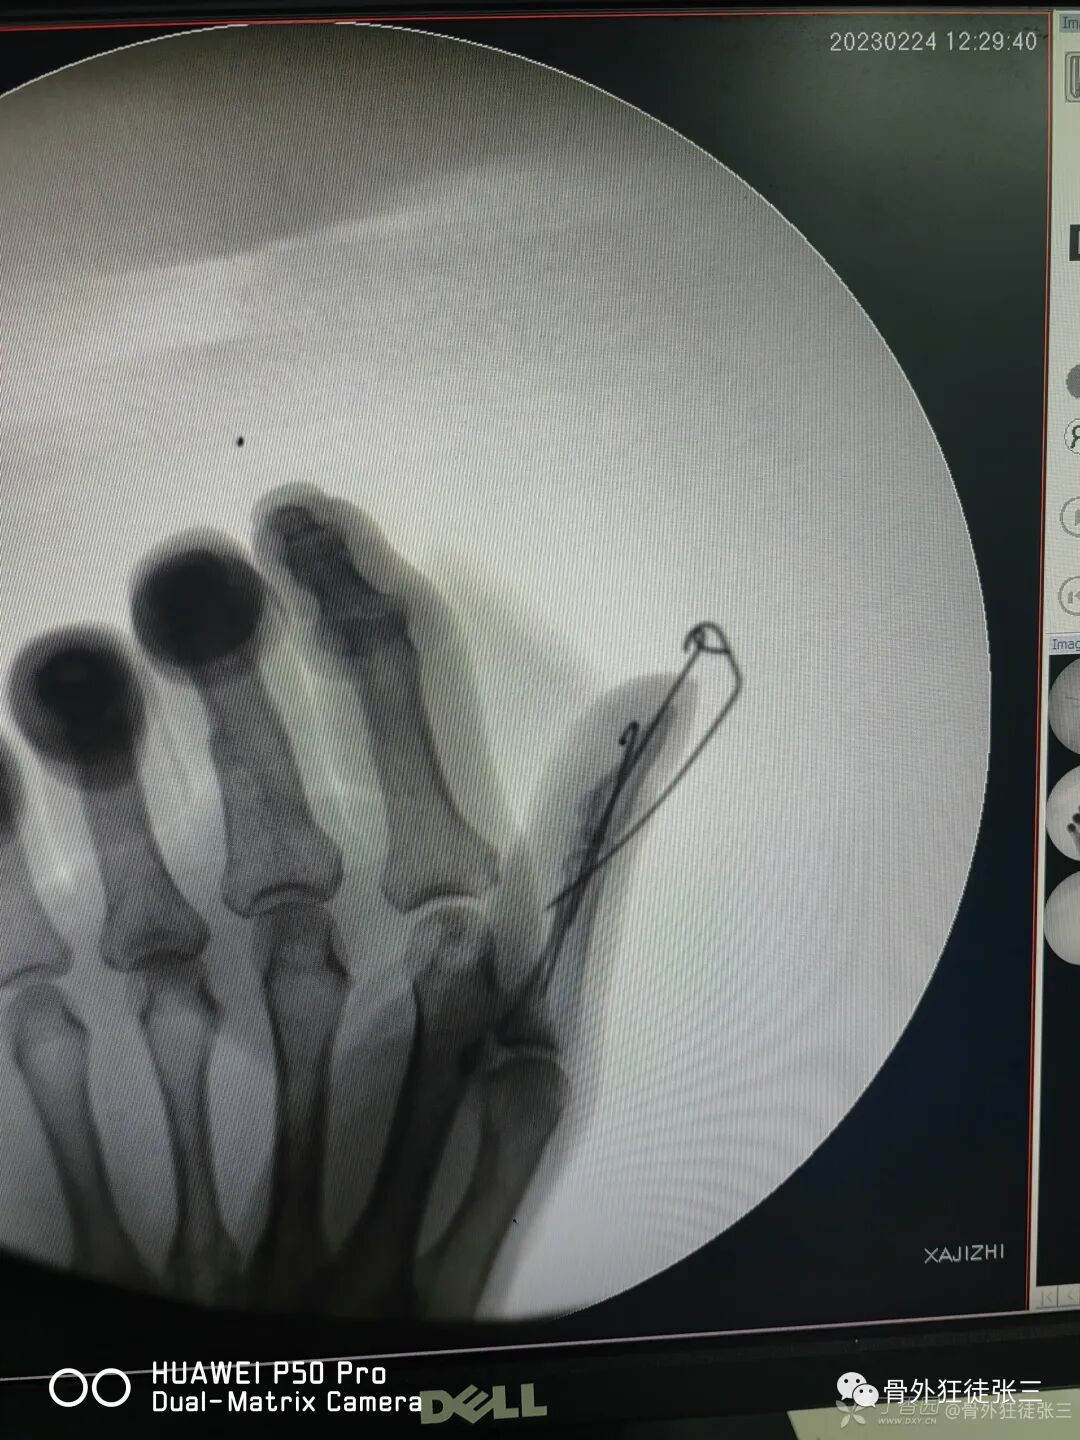

病例41,伸肌腱止点撕脱骨折,石黑法,阻挡克氏针

病例51,伸肌腱止点撕脱骨折,石黑法演示